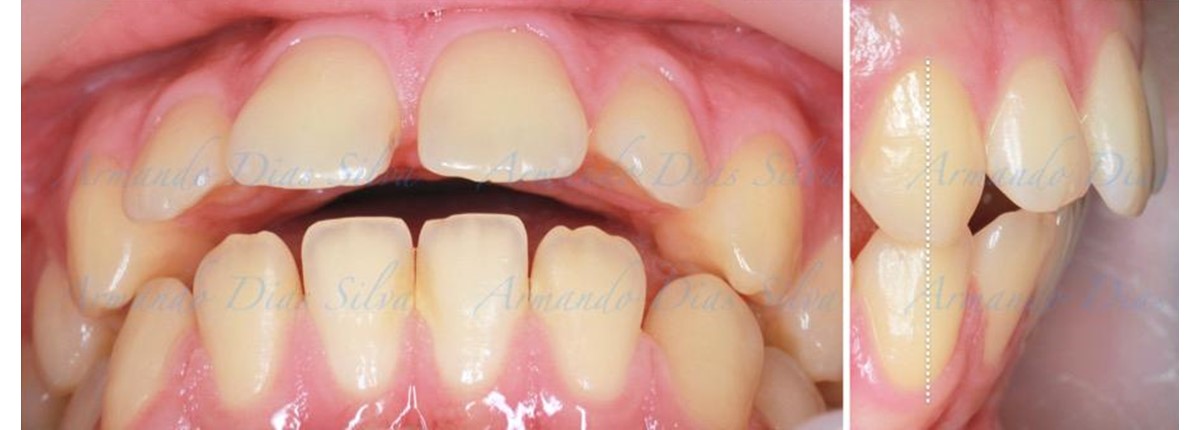

• Molares de clase II

• Diastema

• Espaciamiento leve de las arcadas superior e inferior (deficiencia transversal de 3,45 mm)

• El primer molar superior derecho está en una posición más mesial que el primer molar superior izquierdo

• Incisivos superiores e inferiores proclinados

• Orientación canina desfavorable